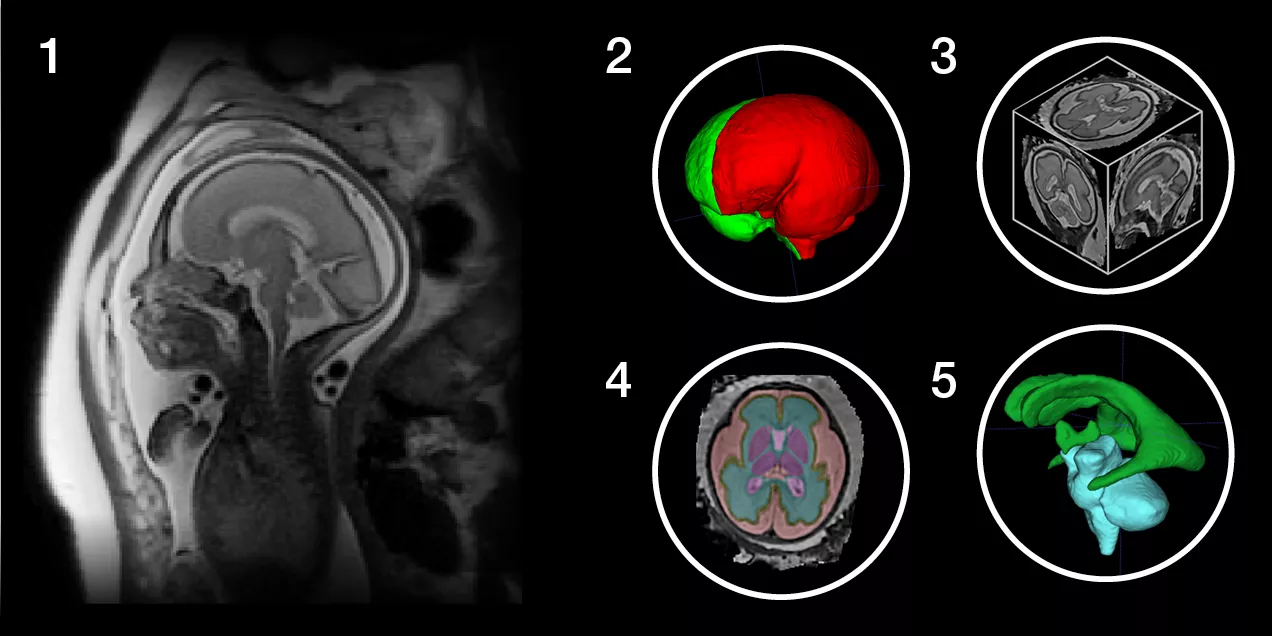

Fetal brain MRI with segmented anatomical regions and 3D visualizations

Fig. 1: Sagittal 2D Image of the fetal brain within the Maternal Abdomen Fig. 2: Volumetric Rendering of the Fetal Brain after 3D Reconstruction Fig. 3: Graphical Representation of the 3D Volume after Slice-to-Volume Reconstruction of 2D Stacks Fig. 4: Axial section of the reconstructed fetal brain overlaid with AI-based tissue parcellations. Red – Subarachnoid space; Yellow – Cortical Gray Matter; Blue – White Matter; Pink – Deep Gray Matter Fig. 5: Ventricular system and brainstem rendered as volumes from the tissue segmentation output. Green – Ventricles; Teal – Brainstem and Cerebellum